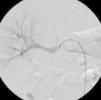

Non-invasive 24-hour blood pressure monitoring revealed stage I hypertension (mean daytime blood pressure 156/87mmHg). Hormonal and imaging studies were also performed for etiologic diagnosis of his hypertension, as well as a captopril test, which was positive for renovascular hypertension. Following this result, renal angiography was performed, which revealed, bilaterally, two renal arteries, and in addition, to the right, depending on the superior artery, three saccular aneurysms 14mm, 6mm and 3.5mm in size. The largest aneurysm appeared to compress the lower polar artery (Figure 1). The aneurysms were treated with placement of a polytetrafluoroethylene (PTFE)-coated stent, in order to prevent expansion and rupture of the aneurysms and to treat the hypertension. Digital subtraction angiography was performed using a right femoral approach. A 65cm 4F sheath was introduced, and the right renal artery was engaged with a 4F Cobra catheter and a 0.014-inch hydrophilic guidewire. Aneurysm morphology was assessed using conventional angiography and flat-panel computed tomography. Stent diameter and length were determined from a three-dimensional flat-panel rotational angiography data set. After administration of 5000 IU of heparin, the aneurysm was crossed with the guidewire and catheter. The wire was exchanged through the same catheter with a 0.014-inch guidewire. Finally, a 6×22-mm covered Atrium stent was deployed, bridging the aneurysm and covering the artery, resulting in successful exclusion of the aneurysms (Figures 2 and 3). The patient was admitted the day before the procedure and was discharged the day after, medicated with 100mg aspirin and 75mg clopidogrel/day, as dual antiplatelet therapy. Ten months after the procedure the patient was asymptomatic, with normal blood pressure and without antihypertensive therapy.

The procedure was uneventful and the final images show the successful exclusion of the aneurysms. Ten months after the procedure, the absence of symptoms and normalization of blood pressure show the success of the intervention.